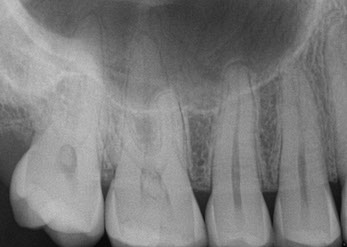

HD Digital X-ray Root Canal & Crown